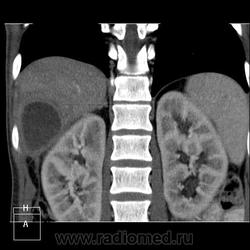

КТ (часть кадров выложу позже ). Цель направления на КТ - образование правой доли печени, исключить образование тела п.ж.

). Цель направления на КТ - образование правой доли печени, исключить образование тела п.ж.

В моче сахар и немного ацетона (цифр не скажу, не помню). Лейкоцитурии и гематурии нет. А я вот по почкам патологии не вижу (точнее не знаю ), есть ли в почках признаки хр.пиелонефрита, о которых УЗИсты написали? Свое заключение уже написала в истории. Жду версий уважаемых коллег))

), есть ли в почках признаки хр.пиелонефрита, о которых УЗИсты написали? Свое заключение уже написала в истории. Жду версий уважаемых коллег))

ну как же? они же как миним огромны. А только артериальная фаза?

Дык три же фазы))). А большие почки - лучше, чем мелкие

у меня недоразвитое представление об артериальной, венозно-паренхиматозной, отсроченных фазах.. Мне показалось, что тут я вижу только корковый слой (на примере почек, опустив факт контрастирования v.cavum). Брюшную полость мне довелось видеть дай бог раза четыре, при этом 2 рака почек, 1 норма и 1 дообследование с контрастом... Так хочется больше и больше наблюдений, что аж зубы сводит-))

В данном случае ранняя артериальная получилась с брачком - контрастировалась нижняя полая (25 сек задержка, триггера нет), панкреатическая 45 сек (стандарт), портальная 70 сек. Отсроченная в печени делается на подозрение на холангиокарциному и гемангиому. Тут почки и не интересовали.

Гепатоспленогмегалия. Начальная портальная гипертензия, холедох не расширен. В воротах печени бугристая масса.... чего? Кальцинаты поджелудочной железы, мелкий камушек в желчном. Вопрос в том, что за кистовидное образование, что за полоса-серп вокруг желчного пузыря, что в воротах печени. Опухоли п.ж. я не нашла.

Данному пациенту в заключении я выставила подпеченочный абсцесс, гепатоспленомегалию, портальную гипертензию, конгломерат лимфоузлов ворот печени, лимфаденопатию желудочной группы л/у, хр.калькулезный панкреатит, ЖКБ с перихолециститом.

С почками стоит подумать.